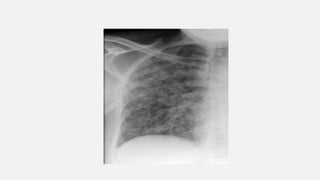

• #12  image of the right lung showing numerous ill-defined nodules in a patient with disseminated pulmonary tuberculosis.